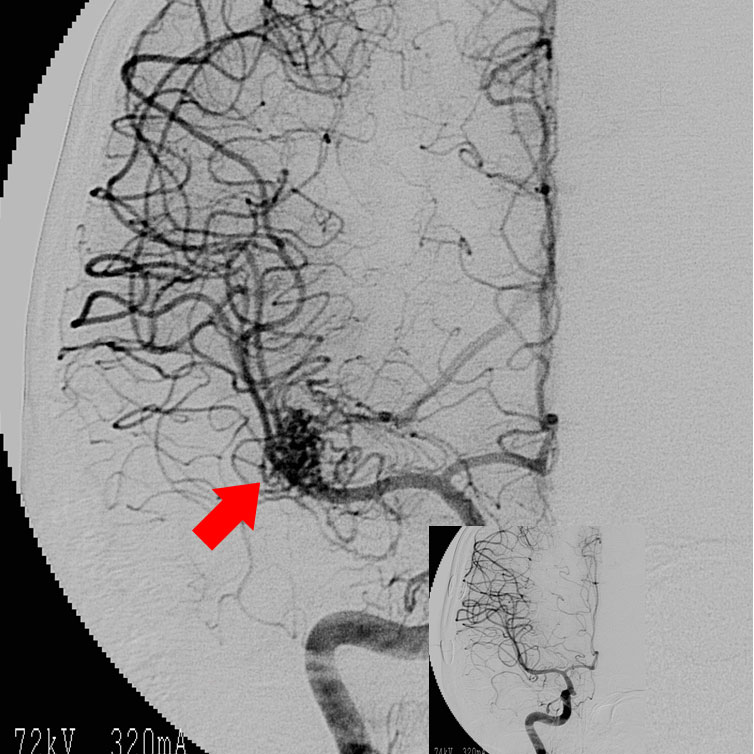

脳動静脈奇形

脳動静脈奇形は先天性の血管奇形のひとつで脳出血や痙攣発作の原因となります。最も基本的な治療法は手術による全摘出ですが、大きさ、発生場所等によっては放射線治療が選択される場合もあります。

当科では放射線治療班と症例検討を行い、個々の患者さんに最も適切は治療を提供しています。 脳動静脈奇形の手術では、術中脳血管撮影を常に行い、全摘出を確認しています。また場合によっては脳動脈瘤手術同様に電気生理学的モニタリングも併用し、確実、安全な手術を行っています(図7、8)。